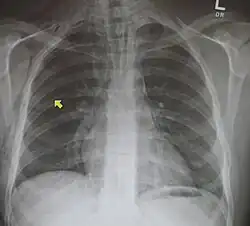

Das Mediastinalemphysem oder auch Pneumomediastinum ist eine Luftansammlung im Mittelfellraum (Mediastinum), die immer Zeichen einer Erkrankung oder Verletzung ist.[1]

Die Diagnose eines Pneumomediastinums wird mittels Bildgebung, entweder mittels konventioneller Röntgenaufnahme (Röntgen-Thorax) oder mittels Computertomographie des Brustkorbs, gestellt. Die Computertomographie ist sensitiver als das konventionelle Röntgen. Neben dem Nachweis auch kleinster Luftansammlungen im Mediastinum liefert die Computertomographie auch Hinweise auf die mögliche Ursachen (Ätiologie).